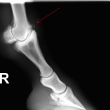

Ankylóza spěnkovýho kloubu

rentgenologické vyšetření

ohebové zkoušky